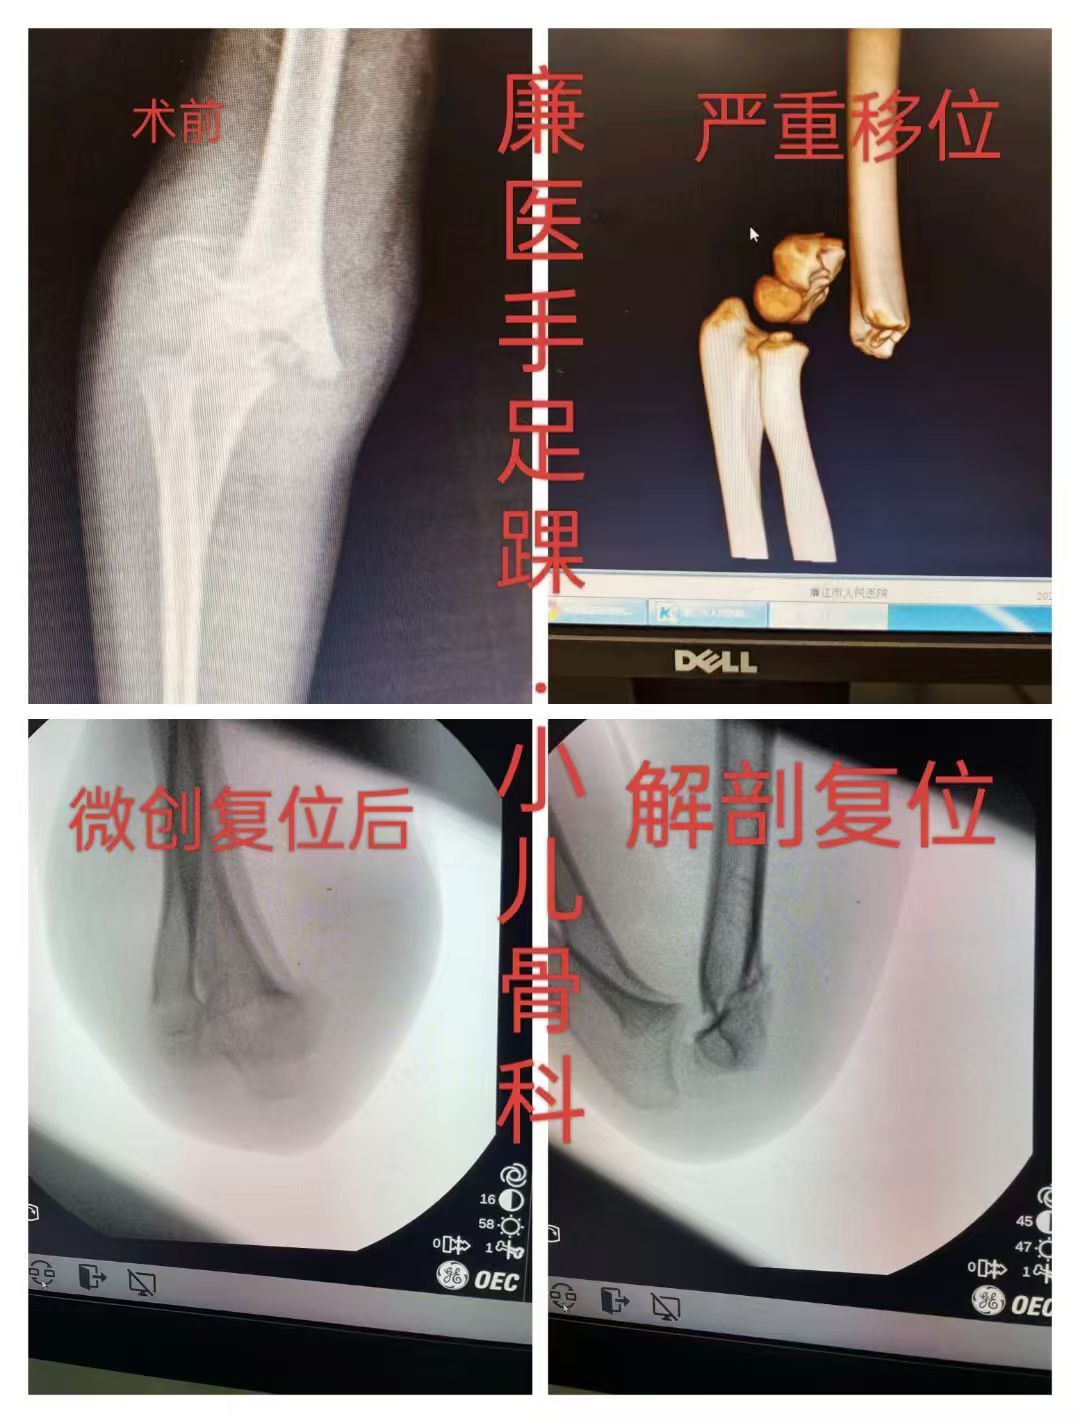

图片

图片图片

小儿肱骨髁上骨折闭合复位微创经皮骨针内固定